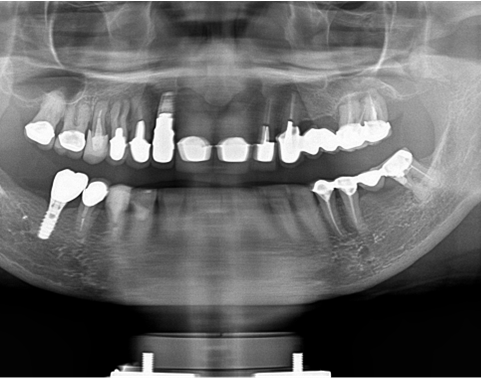

予定通りジルコニアクラウンにて、インプラント修復が行えました。

レントゲン写真でも理想的な位置

に埋入できました。

術前ではインプラントを埋入する骨組織はほとんど有りませんが、

術後完全に骨内に埋入出来ました。